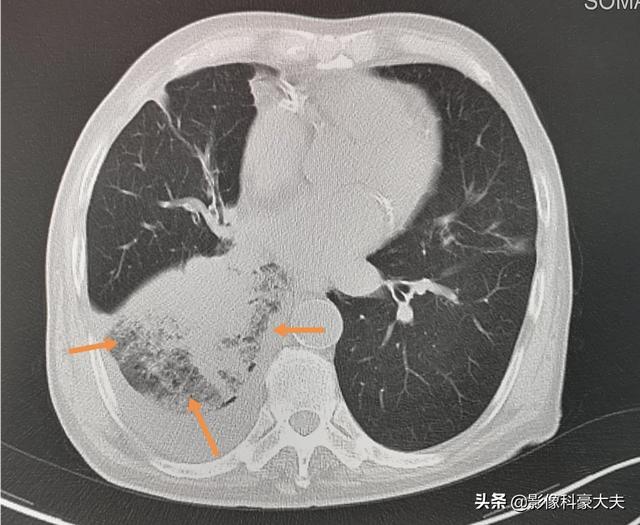

これは79歳の男性で、4年前から小細胞肺がんを患っている。右下葉の気管支が狭くなっているため、閉塞性肺炎を引き起こし、高熱を繰り返す。